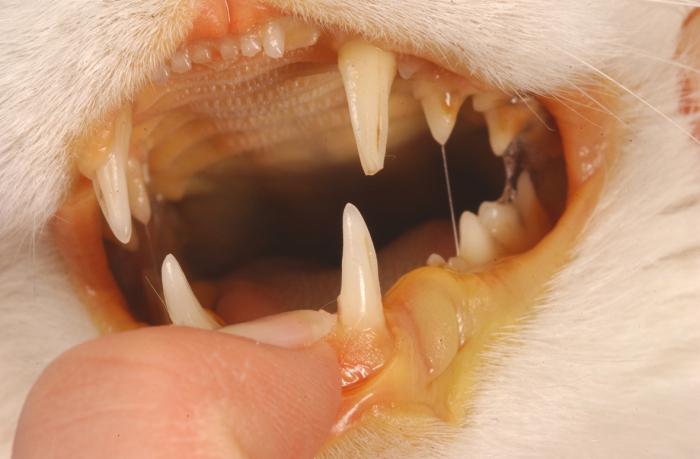

Гнойные выделения из носа и глаз являются характерным признаком микоплазмоза.

При поражении суставных элементов наблюдается нарушение двигательных функций животного, что отчетливо отслеживается по его походке – кошка хромает, поджимает лапки, долго не может находиться в стоячем положении.